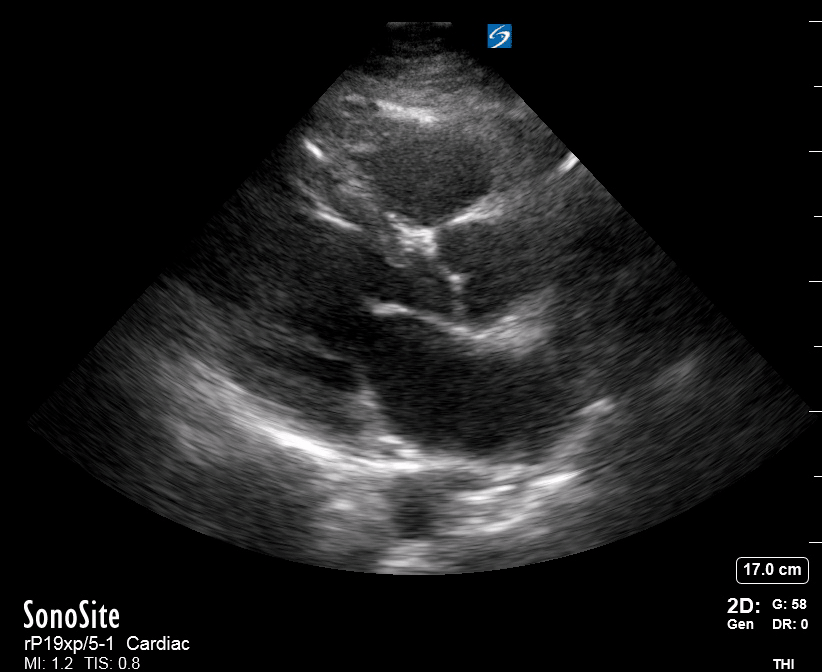

Equality: is the RV dilated or significantly impaired?

Normally, the RV is a low-pressure, thin-walled, high-compliance chamber that wraps anteriorly around the muscular, cone-shaped LV. The normal RV : LV diameter ratio is 0.6 : 1.

When the pulmonary artery pressure rises, the RV will dilate, altering the normal RV:LV ratio. Although sacrificing sensitivity, the use of equality (1:1 ratio) as a cutoff can achieve a specific estimation of RV strain. If imaged correctly by a trained operator, the presence of an RV:LV ratio > 1 is highly specific for RV strain.

RV dilation can be acute, chronic, or acute-on-chronic. However, in patients presenting with undifferentiated chest pain, shortness of breath, hypotension or syncope, the presence of any RV dilation should raise suspicion for acute pulmonary embolism (PE). Furthermore, in a patient in shock, the presence of RV strain may signal the need for aggressive therapy – emergency thrombolysis.

THE VIEWS

The A4C view provides an accurate chamber size comparison. However, achieving a proper A4C view (avoiding foreshortening or ballooning, and visualising the four chambers with a vertically oriented interventricular septum) can be a challenging exercise of image acquisition. Additionally, the PSAX view at the level of the papillary muscles shows both LV and RV side by side and is useful to assess function and size. When RV pressure is high, the septum will be pushed and flattened towards the LV, resulting in the characteristic “D-shaped” LV or “D sign”.